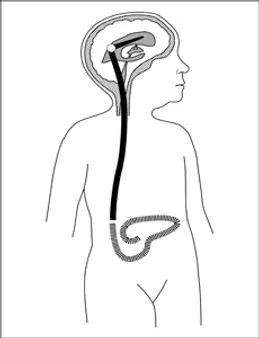

Önceden yerleştirilen bir kateter aracılığıyla belirli aralıklarla yaklaşık 2 litrelik diyaliz sıvısının karın boşluğuna doldurulması, bekletilmesi ve boşaltılması şeklinde uygulanan bir diyaliz yöntemidir. Kanda birikime uğrayan atık maddeler ve sıvı fazlası periton zarını geçerek karın boşluğundaki diyaliz sıvısına geçer ve boşaltılan diyaliz sıvısı ile de vücuttan uzaklaştırılır. Periton diyalizi tedavisi için, olası diyaliz zamanından yaklaşık 3 hafta karın boşluğuna silikondan yapılmış yumuşak bir kateterin yerleştirilmesi gerekir. Kateter yerleştirme işlemi ameliyathanede cerrahi olarak ve yatak başında yapılabilir.

Böbrek naklinden önce böbrek alıcı ve vericilerinde belli incelemelerin yapılması gerekir. Nakledilen böbrek sağ veya sol kalça kemiği boşluğuna yerleştirilir. Eğer herhangi bir sorun yoksa, hastanın kendi böbrekleri yerinde bırakılır.